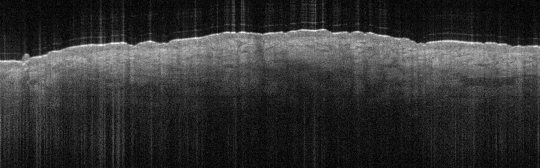

VA38: Upper Forehead, Left of Midline, Actinic Keratosis, Hypertrophic

- Arrows indicate base of epidermal thickening

VA36: Upper Forehead, Left of Midline, Adjacent, Normal